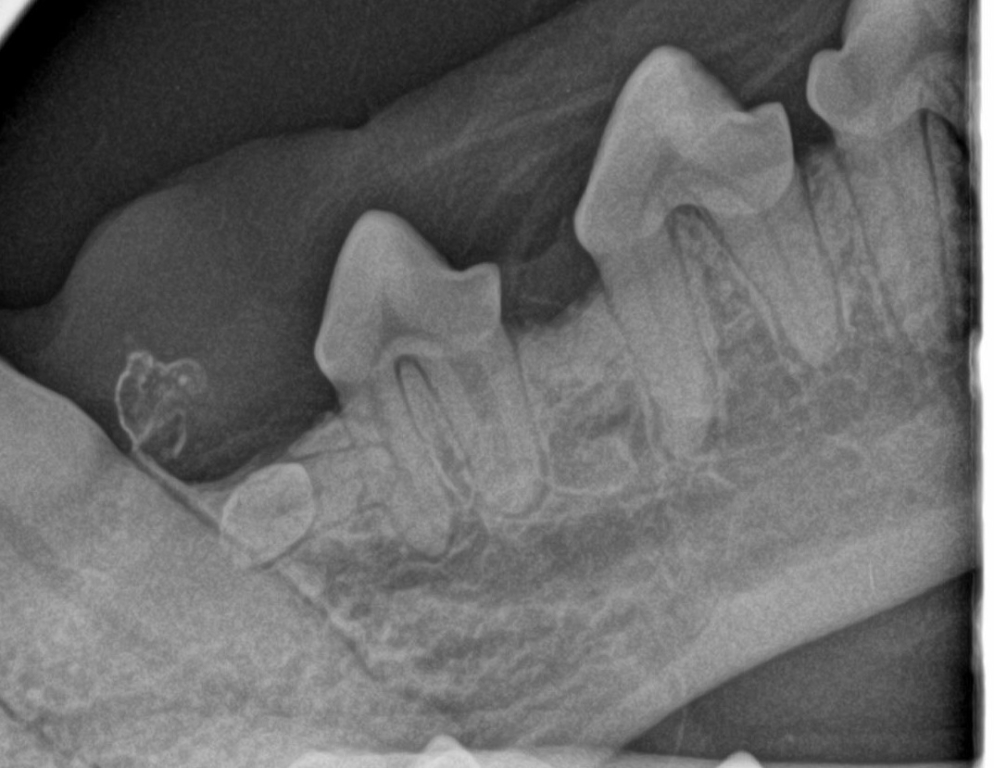

Dental radiography is a key tool for clinicians to accurately examine teeth. Research has highlighted that 42% of cats and 28% of dogs have lesions[i] which are only detectable on x-ray. Failing to identify teeth with root lesions can have a significant negative outcome for patient welfare, causing ongoing pain and eventual tooth loss.

An audit of each participating practice’s dental radiology data was conducted at the start of the project. Results were then shared with each practice every month. One year on, data shows that 43% of dental cases in project practices are now using dental radiography as part of their consultation. In the best cases, some practices have been in 100% of cases.

“When you open a patient’s mouth and look inside, seemingly normal teeth are oftentimes not normal. So vets and nurses can risk missing periodontal disease.

“Dental radiology has historically been underutilised but we believe it adds valuable information to dental consultations and is an important decision-making tool.